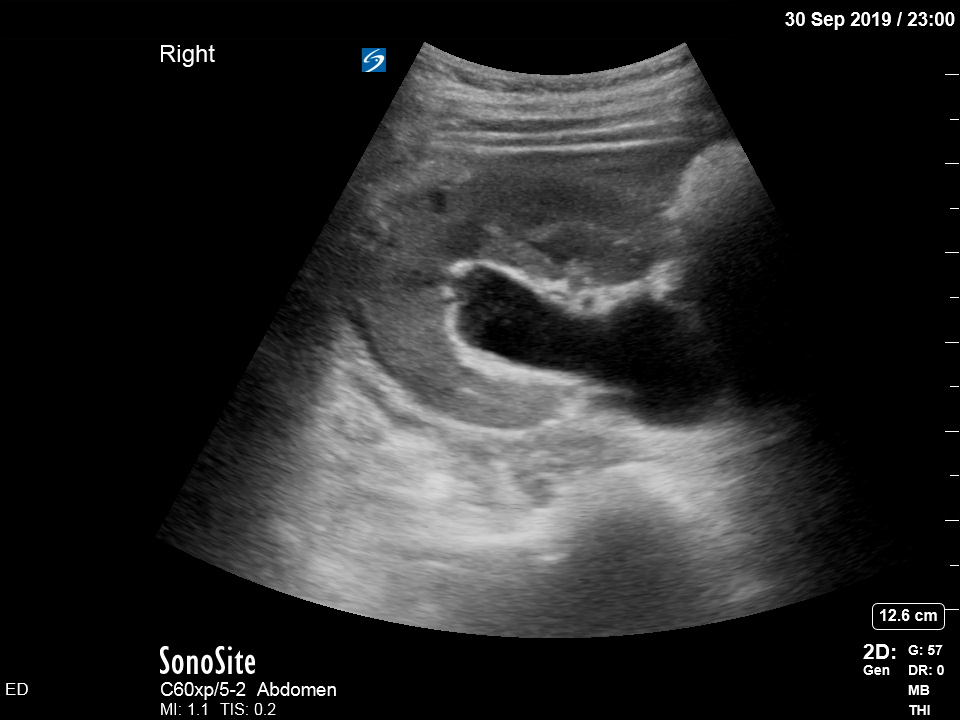

Bedside ultrasound was undertaken to assess for signs of ureteric obstruction.

There is moderate-to-severe hydronephrosis of the right kidney. There is mild hydronephrosis on the left. Colour flow doppler is used to demonstrate that the dilated pelvis and calyces are not normal blood vessels or aneurysms.

Hydronephrosis is dilation of the renal collecting system caused by increased pressure in the ureter, strongly suggesting downstream obstruction. Possible explanations for bilateral hydronephrosis include bladder outlet obstruction and bilateral ureteric obstruction. The former is unlikely in a freely urinating patient, especially female.

The history and findings suggest that the patient has developed bilateral ureteric obstruction from progression of retroperitoneal disease.